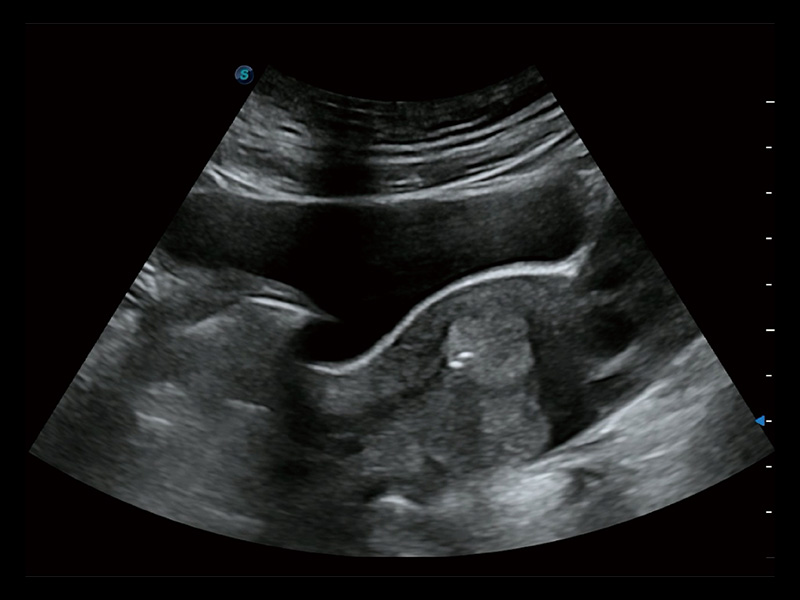

超声引导下双侧卵巢穿刺取卵

卵巢多囊样改变